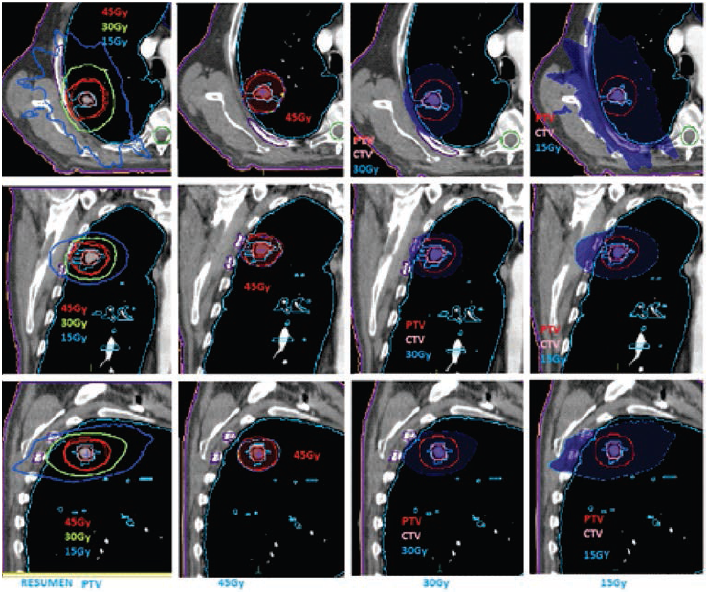

El tratamiento se realizó en un acelerador lineal Elekta Axesse a partir del 20 de diciembre 2013 con imágenes XVI (rayos X volumétricos). Previo a cada sesión, se realizaron correcciones traslacionales y rotacionales. La dosis total suministrada fue de 45 Gy en 3 fracciones, cada una de 15 Gy por día (figura 1 y tabla 1).

En cortes tomográficos axiales, coronal y sagitales: observamos el adecuado cubrimiento de la dosis prescrita (isodosis color rojo) y el rápido arrastre de la dosis por fuera del PTV